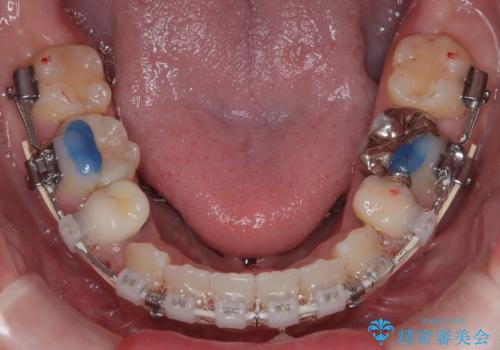

- 治療計画

抜歯によって前歯を下げるためのスペースを確保。その後、審美ワイヤー矯正を用いて、歯列全体のバランスを整えながら前歯を後方へ移動させました。治療後は、横顔のラインが整い、自然な口元になったことで、見た目も噛み合わせも改善しました。患者様からは「口元がすっきりして、自信を持って笑えるようになった」と喜びの声をいただきました。